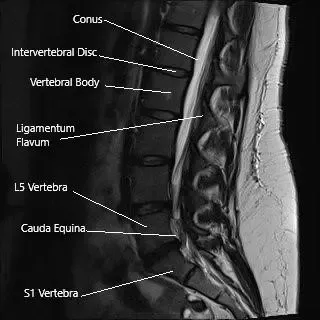

Sección sagital de la columna lumbosacra en la resonancia magnética.

Los exámenes radiológicos de la cadera suelen incluir una radiografía, que puede o no ser seguida por una resonancia magnética o un TAC. El diagnóstico de patologías espinales que causan ciática suele requerir una resonancia magnética. Una resonancia magnética es capaz de diferenciar entre las estructuras de tejidos blandos como nervios, ligamentos, discos intervertebrales, etc.